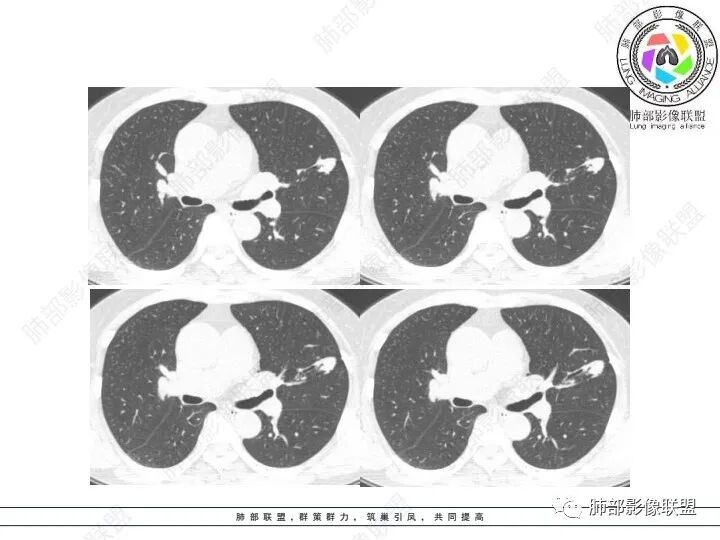

1、临床特点:61岁女性,体检发现肺结节。

2、影像特点:左肺上叶不规则病灶,冠状位、矢状位、斜状位重建显示病 灶整体沿着支气管方向呈斑片状,多结节堆积感明显,病灶大部分边缘显示平直,局部边缘稍膨隆,边界显示比较清楚,近端支气管壁显示增厚,周围可见长索条影及多发结节影,未显示典型“树芽征”。邻近叶间裂未受牵拉凹陷。纵隔窗显示病灶中央可见点状高密度钙化影。

3、病例小结:老年女性体检发现肺部结节,缺乏临床表现,需要警惕恶性。结合影像特点,左肺上叶病灶整体缺乏膨隆感,边缘大多平直,周围多发卫星灶(可见多发长索条影、并非肺CA的细短毛刺),病灶收缩力很弱(邻近叶间裂未见明显凹陷),观察1mm重建图亦可以发现病灶周围没有边界清楚的GGO,病灶内可见钙化点,肺门纵隔未见肿大淋巴结。综合以上,此病灶首先考虑炎性,结核可能性大,有条件可以增强扫描,有助于我们进一步判断。